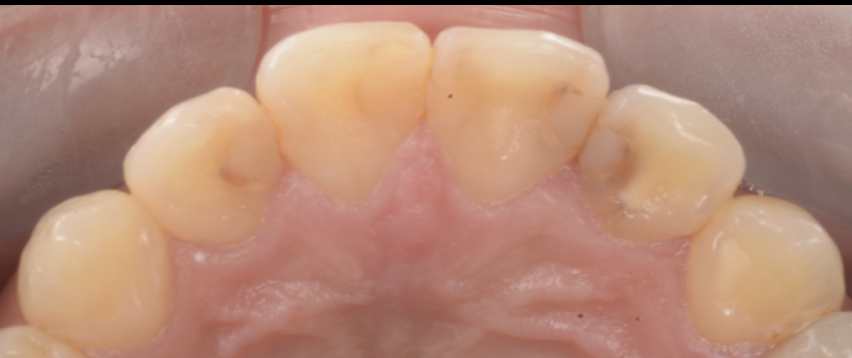

【池袋の症例】主訴:前歯の色/「虫歯があると言われた」

今回の患者さんは、上顎前歯部について

- 「前歯の色が気になる」

- 「虫歯があると言われた」という不安を抱えて来院されました。

前歯は目につきやすく、少しの着色でも気になります。

ただし、ここで重要なのは「見た目の色=虫歯」とは限らないこと、そして「色だけ」と決めつけるのも危険だということです。

なぜなら、接着が壊れている場合、見た目の変色の奥で感染が進んでいることがあるからです。

初診時に疑うポイント

- 修復物の辺縁に着色(マージンステイン)

- 詰め物が浮いて見える、段差が疑われる

- 見た目よりも内部で進行している可能性

今回も、色の違和感をきっかけに精査し、修復物を外してみると、想定以上に内部で感染が広がっていました。

つまり、「色が気になった」という主訴は、結果的に歯を守るための重要なサインだったといえます。